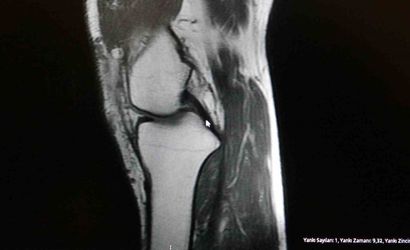

Ortopedi polikliniklerine en sık başvuran yaralanmaların ayak bileği, diz ve omuzda olduğunu belirten Demirbaş, futbolun yaralanma oranlarının en yüksek olduğu branşlardan biri olduğunu ifade etti. Bu bağlamda, menisküs yırtıkları, ön çapraz bağ yırtıkları ve aşil tendon kopmalarının sık görüldüğünü söyledi.